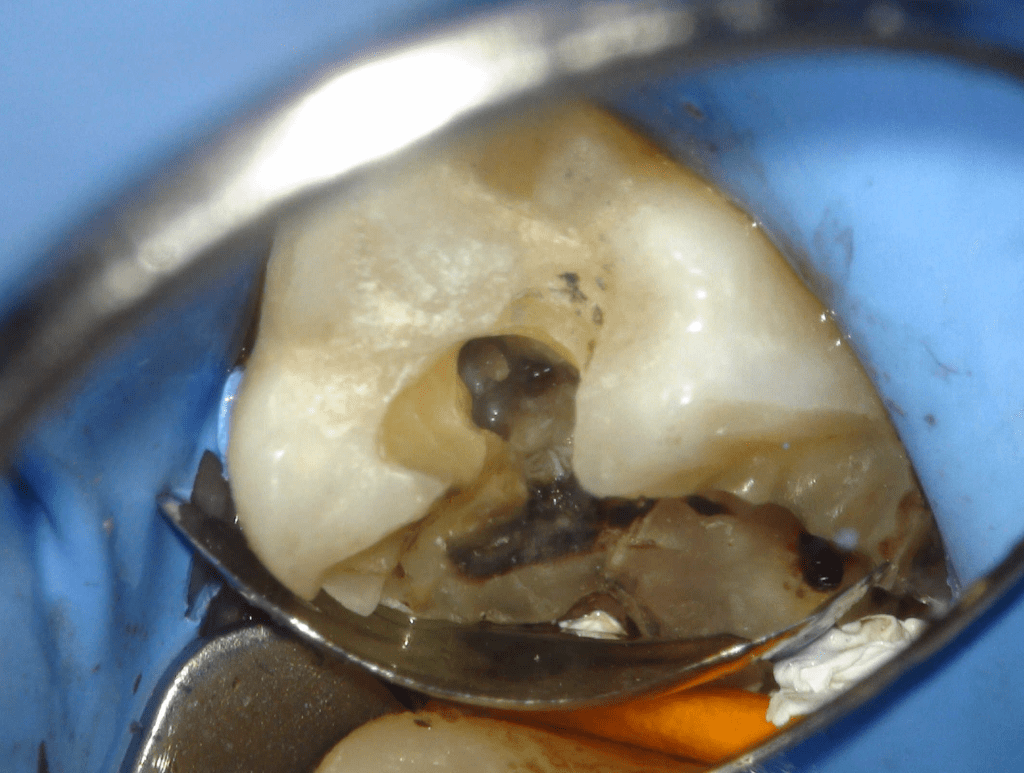

Fisura, remoción amalgama para explorar